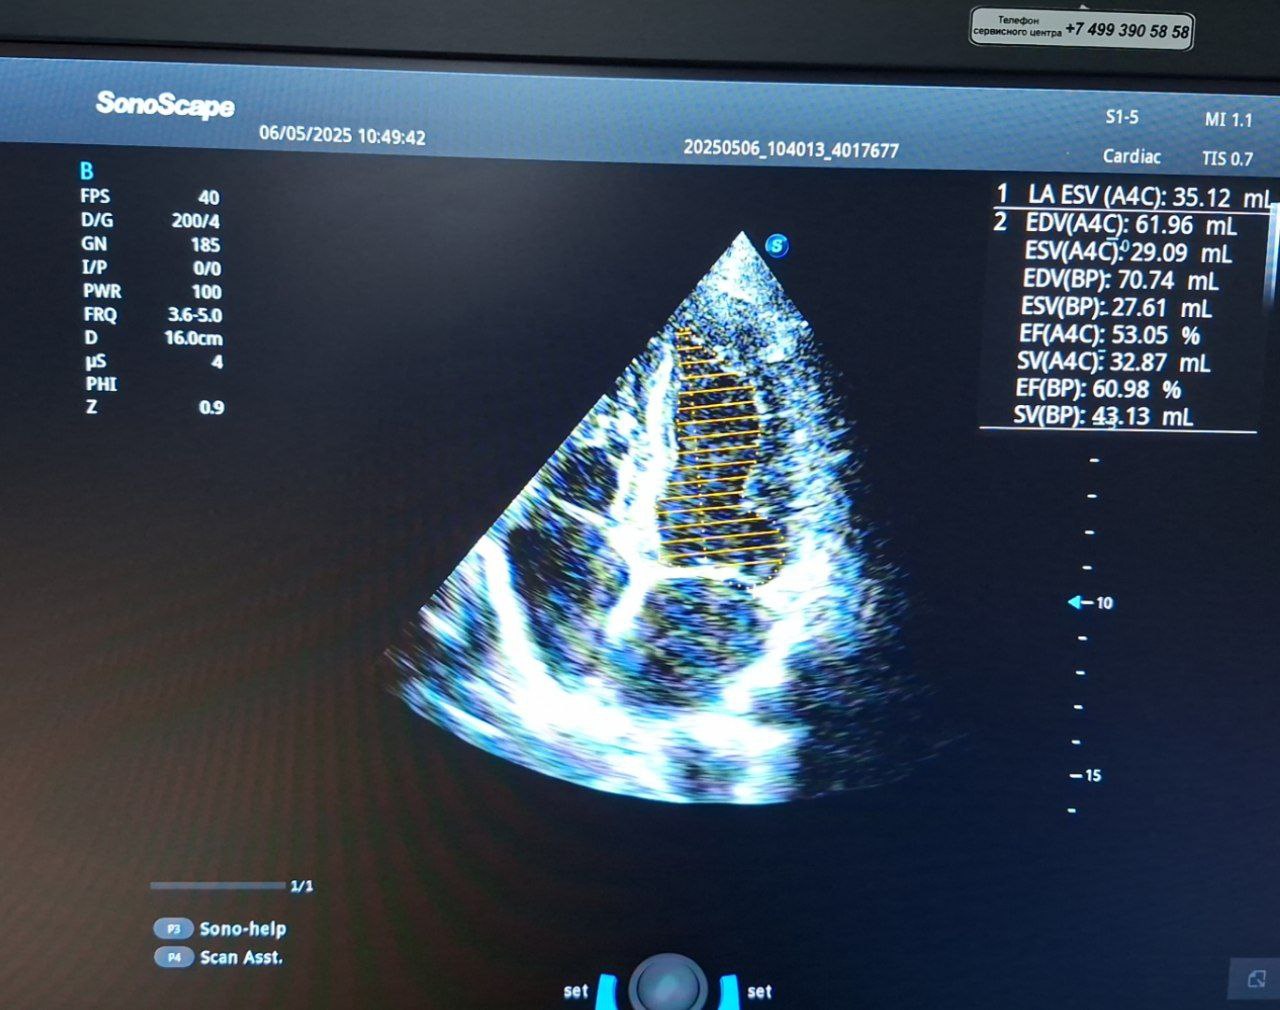

МРТ сердца: Выявлено трансмуральное (на всю толщину стенки) рубцовое поражение миокарда в бассейне ПМЖВ, сформирована акинетическая аневризма верхушки сердца (участок не сокращается и выбухает). Фракция выброса (ФВ) левого желудочка снижена до 52%. Конечно-систолический объем ЛЖ увеличен. Гипертрофии миокарда нет.

ЭхоКГ: Незначительная дилатация (расширение) корня аорты. Полости сердца не расширены. Гипертрофии миокарда ЛЖ нет.

Ключевая находка: Нарушение локальной сократимости миокарда ЛЖ в виде акинеза (06.05.2025) и гипокинеза (17.12.2025) передне-перегородочного среднего и верхушечного сегментов, что соответствует данным МРТ об аневризме верхушки. Фракция выброса ЛЖ: 57% (01.2025) -> 63% (05.2025) -> 68% (12.2025) – положительная динамика. Признаки легкой митральной и трикуспидальной регургитации (недостаточности клапанов 1 ст.).

Отмечается субъективное улучшение самочувствия. По данным контрольных эхокардиографических исследований зафиксирован значительный рост фракции выброса левого желудочка с 57% до 68% в течение года, что свидетельствует об улучшении насосной функции сердца. Зона нарушенной сократимости миокарда трансформировалась из акинеза (отсутствие сокращений) в гипокинез (снижение сократимости), что также может указывать на частичное восстановление функции или ремоделирование.